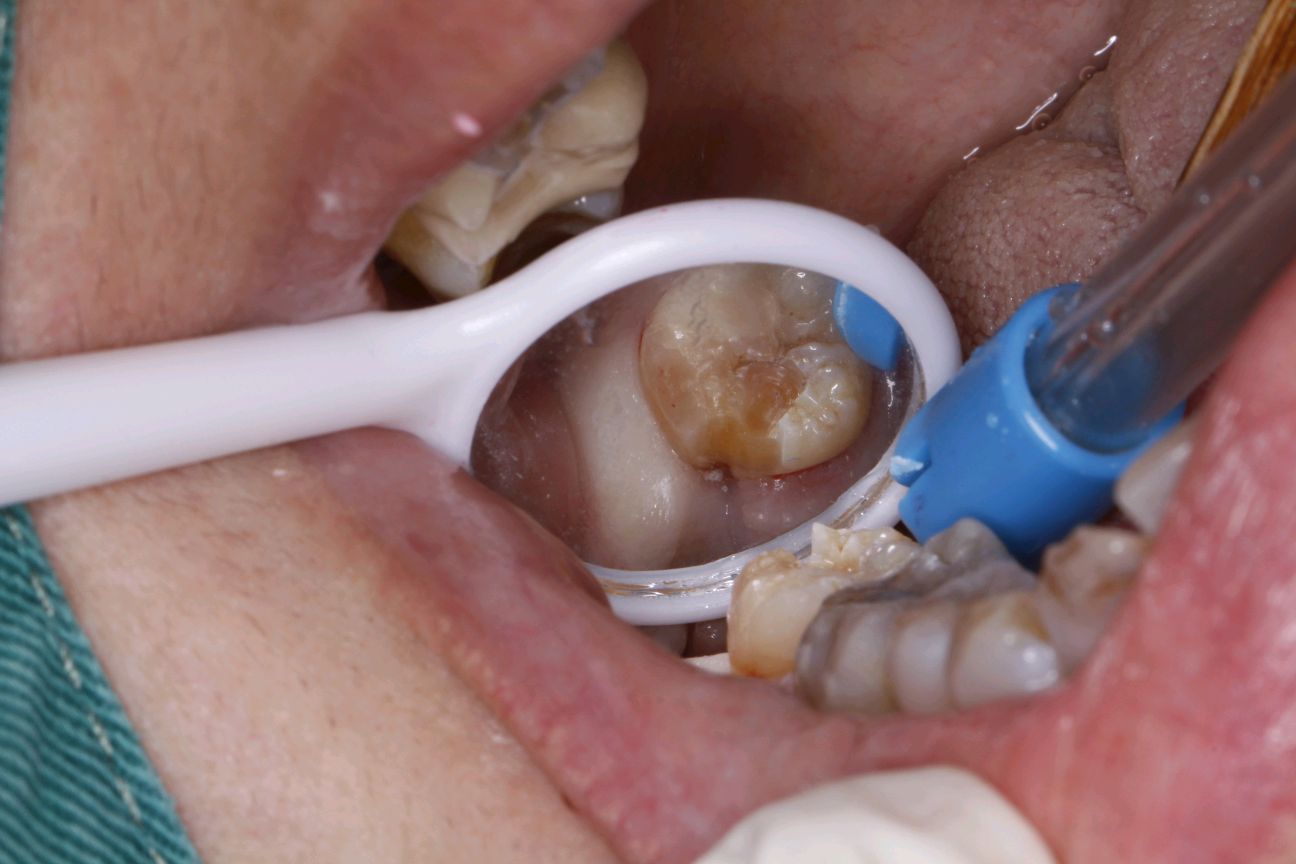

对于以上这些智齿如果不拔除会有哪些危害呢?1、会顶坏邻近牙齿。常常塞牙导致邻牙龋坏或者牙槽骨吸收。2、容易引起智齿冠周炎。智齿萌出不全异位或者阻生。牙龈与牙体之间容易形成一个狭窄较深的盲袋。易积攒食物残渣滋生细菌。时间长了就会造成智齿冠周炎起疼痛,肿胀,张口受限,严重了会导致间隙感染。3、影响咬合。智齿萌出位置异常,导致咬合关系错乱,影响颞下颌关节的正常活动。4、位置靠后不易清洁,食物残渣堆积容易发生龋坏,长期以往会发展成牙髓炎,发生疼痛的现象。

所以对于智齿带来的基本都是烦恼,与其徒增烦恼不如早早杜绝,如果你有智齿还需尽早去医院检查确认是否需要拔除,避免出现不必要的危害。